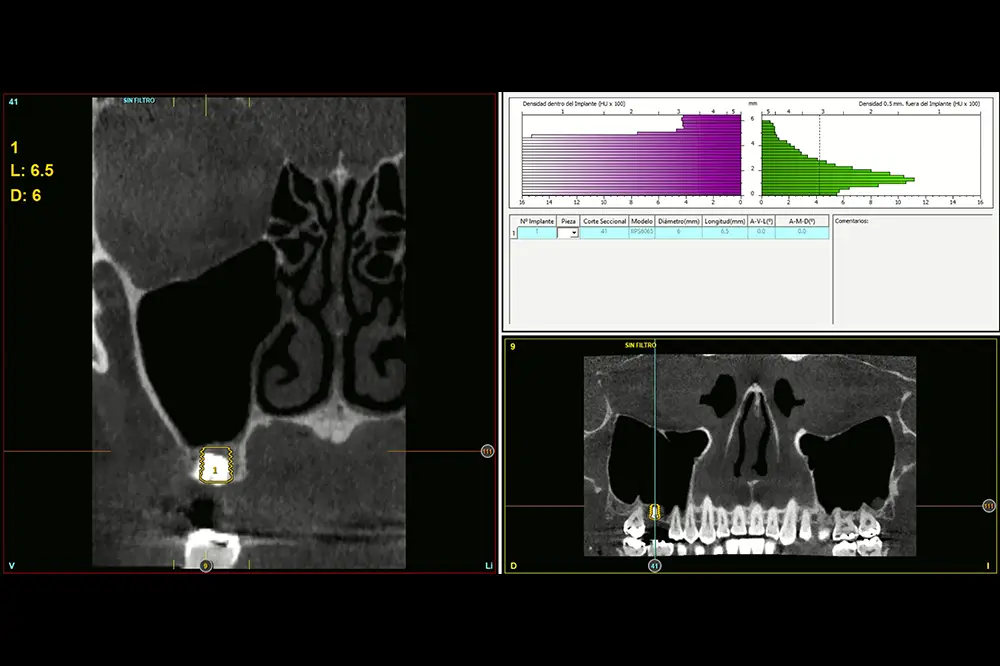

Fig. 3. Medición en el TAC de planificación de la altura del tramo edéntulo para planificar el implante a insertar. Podemos ver cómo en la zona más vestibular únicamente disponemos de 1,5 mm y en la zona más palatina de 3 mm. Esto nos permitirá anclar el implante.

Fig. 4. Planificación del implante de 4,5 mm de longitud. Como vemos, la mayor parte de su anclaje viene dada por la bicorticalidad vestíbulo-lingual y además será utilizado como mantenedor del injerto primario (evitando el colapso) para posteriormente insertar uno de mayor longitud.